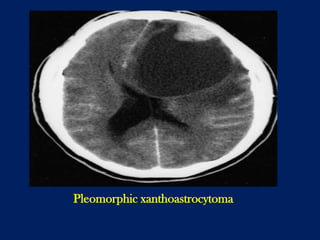

Pleomorphic xanthoastrocytoma